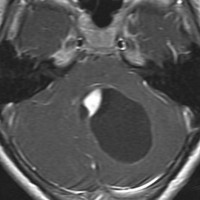

思春期の女の子にできた小脳腫瘍です。とても大きく見えますがほとんどが水たまり(のう胞といいます)。第4脳室が腫瘍で圧迫されて閉塞性水頭症になりました。のう胞の中に出血がありますが毛様細胞性星細胞腫では腫瘍内出血をしばしば見ます。右の写真で脳室が大きくなっています。こんなに大きいのに小脳症状は全くなくて,頭痛と嘔吐が症状でした。

赤で塗ったところだけが毛様細胞性星細胞腫です。これを取れば治ります。簡単な手術ですし後遺症も残りません。

手術後のMRIです。水頭症も改善してますから症状も消失しましたし,すぐに退院です o(^o^)o